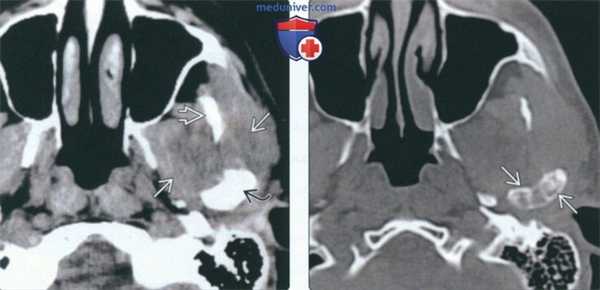

(Слева) КТ в костном окне, аксиальная проекция. Типичная хондросаркома левого височно-нижнечелюстного суаава. Мыщелок нижней челюсти склерозирован и имеет неправильную форму, внутри и вокруг сустава рассеянны множественные кальцификаты. И хотя в данном случае достаточно сложно дифференцировать заболевание от синовиального хондроматоза, в обоих случаях лечение должно быть хирургическим, а точный диагноз будет установлен после гистологического исследования.

(Справа) Реконструкция в сагиттальной плоскости, этот же пациент. Мыщелок деформирован, а часть кальцификатов находится в мягких тканях вне сустава.

(Слева) На аксиальной КТ в костном окне визуализируется типичная хондросаркома ВНЧС с множественными кальцинатами. Мыщелок нижней челюсти слева неравномерно склерозирован, в ВНЧС и вокруг него визуализируются множественные мелкие очаговые кальцинаты.

(Справа) На сагиттальной реформатированной КТ у этого же пациента определяется деформация мыщелка. Некоторые кальцинаты, вероятно, находятся в мягкотканном компоненте за пределами сустава.